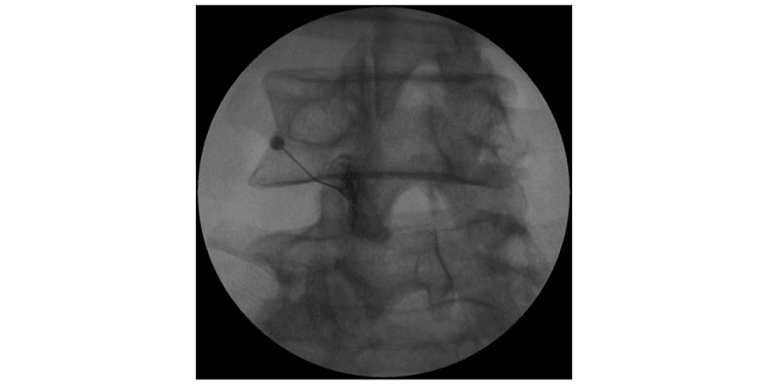

CT scan of a spine shows a needle targeting a spinal area, with an arrow indicating the entry point.

Step 4: Needle Targets Facet Joint

The needle is advanced until it reaches the facet joint capsule. Contrast dye may be injected to confirm proper needle placement within the joint space.